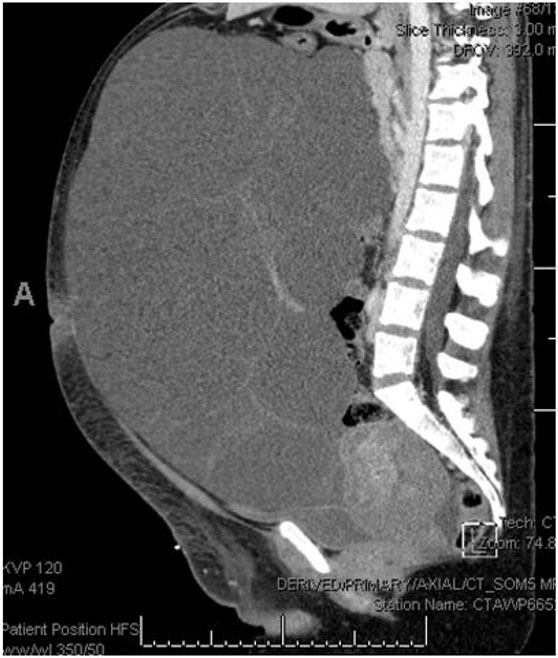

She had an uncomplicated immediate postpartum course and was discharged postpartum day 4 with plan for outpatient follow-up. Serum creatinine was normal at 0.64 mg/dL and urine protein/creatinine ratio was elevated at 0.343. She was discharged with a three day course of Lasix for lower extremity edema but was normotensive at the time of discharge with no anti-hypertensive therapy. Ultimately, she presented to another tertiary hospital emergency department (ED) roughly six weeks postpartum with worsening abdominal pain and abdominal distention. At this encounter, she was again normotensive not on anti-hypertensive therapy with urine protein 20 mg/dL on urinalysis. Transvaginal ultrasound (TVUS) demonstrated large multi-septated cystic mass filling abdomen and pelvis, measuring 35.2 × 31.2 × 16.3 cm (Figure 2). Repeat computed tomography (CT) at that time demonstrated enlargement of bilateral adnexal masses to “large multi-septated cystic mass (vs two large adjacent multi-cystic masses) nearly replacing the entire abdomen and pelvis, measuring 25.1 × 32.1 × 35.7 cm” (Figure 3). She was referred outpatient to Gynecologic Oncology and ultimately underwent exploratory laparotomy, drainage of adnexal masses, bilateral ovarian cystectomy, and reconstruction. She had large, thin walled, multi-septated cysts from both ovaries taking up the entire abdomen and pelvis. Twelve liters of serous appearing fluid was drained intraoperatively and approximately 50–100 cysts were drained individually. Pathology intraoperatively was benign and final pathology demonstrated benign ovarian cysts with features of HL.

Figure 3: CT abdomen and pelvis, non-contrasted, obtained six weeks postpartum, demonstrating mass completely filling abdomen and pelvis.